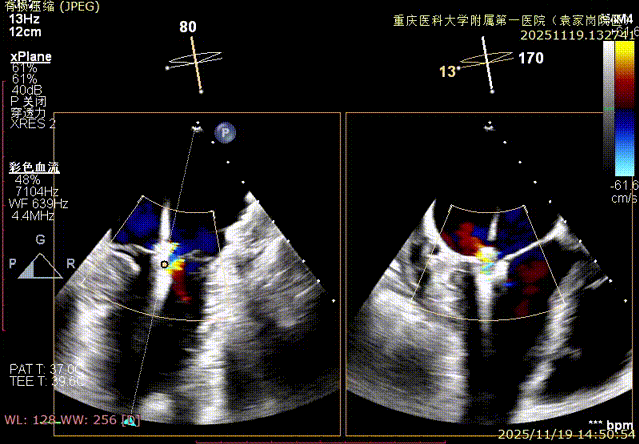

二尖瓣术前评估

复查TTE及TEE检查进一步评估二尖瓣情况。明确为FMR( Carpentier Ⅲb型),二尖瓣后叶栓系,2区瓣叶运动(视频2),重度FMR(4+), 肺静脉逆向血流;2区后叶长度1.15cm,2区前叶长度2.46cm,AP径3.2cm,瓣口面积5.1cm²,房间隔高度3.95cm,瓣叶无钙化,二尖瓣瓣膜条件适合行TEER手术。

图1、图2:2区瓣叶长度(前叶长度2.46cm,后叶长度1.15cm)及彩色血流